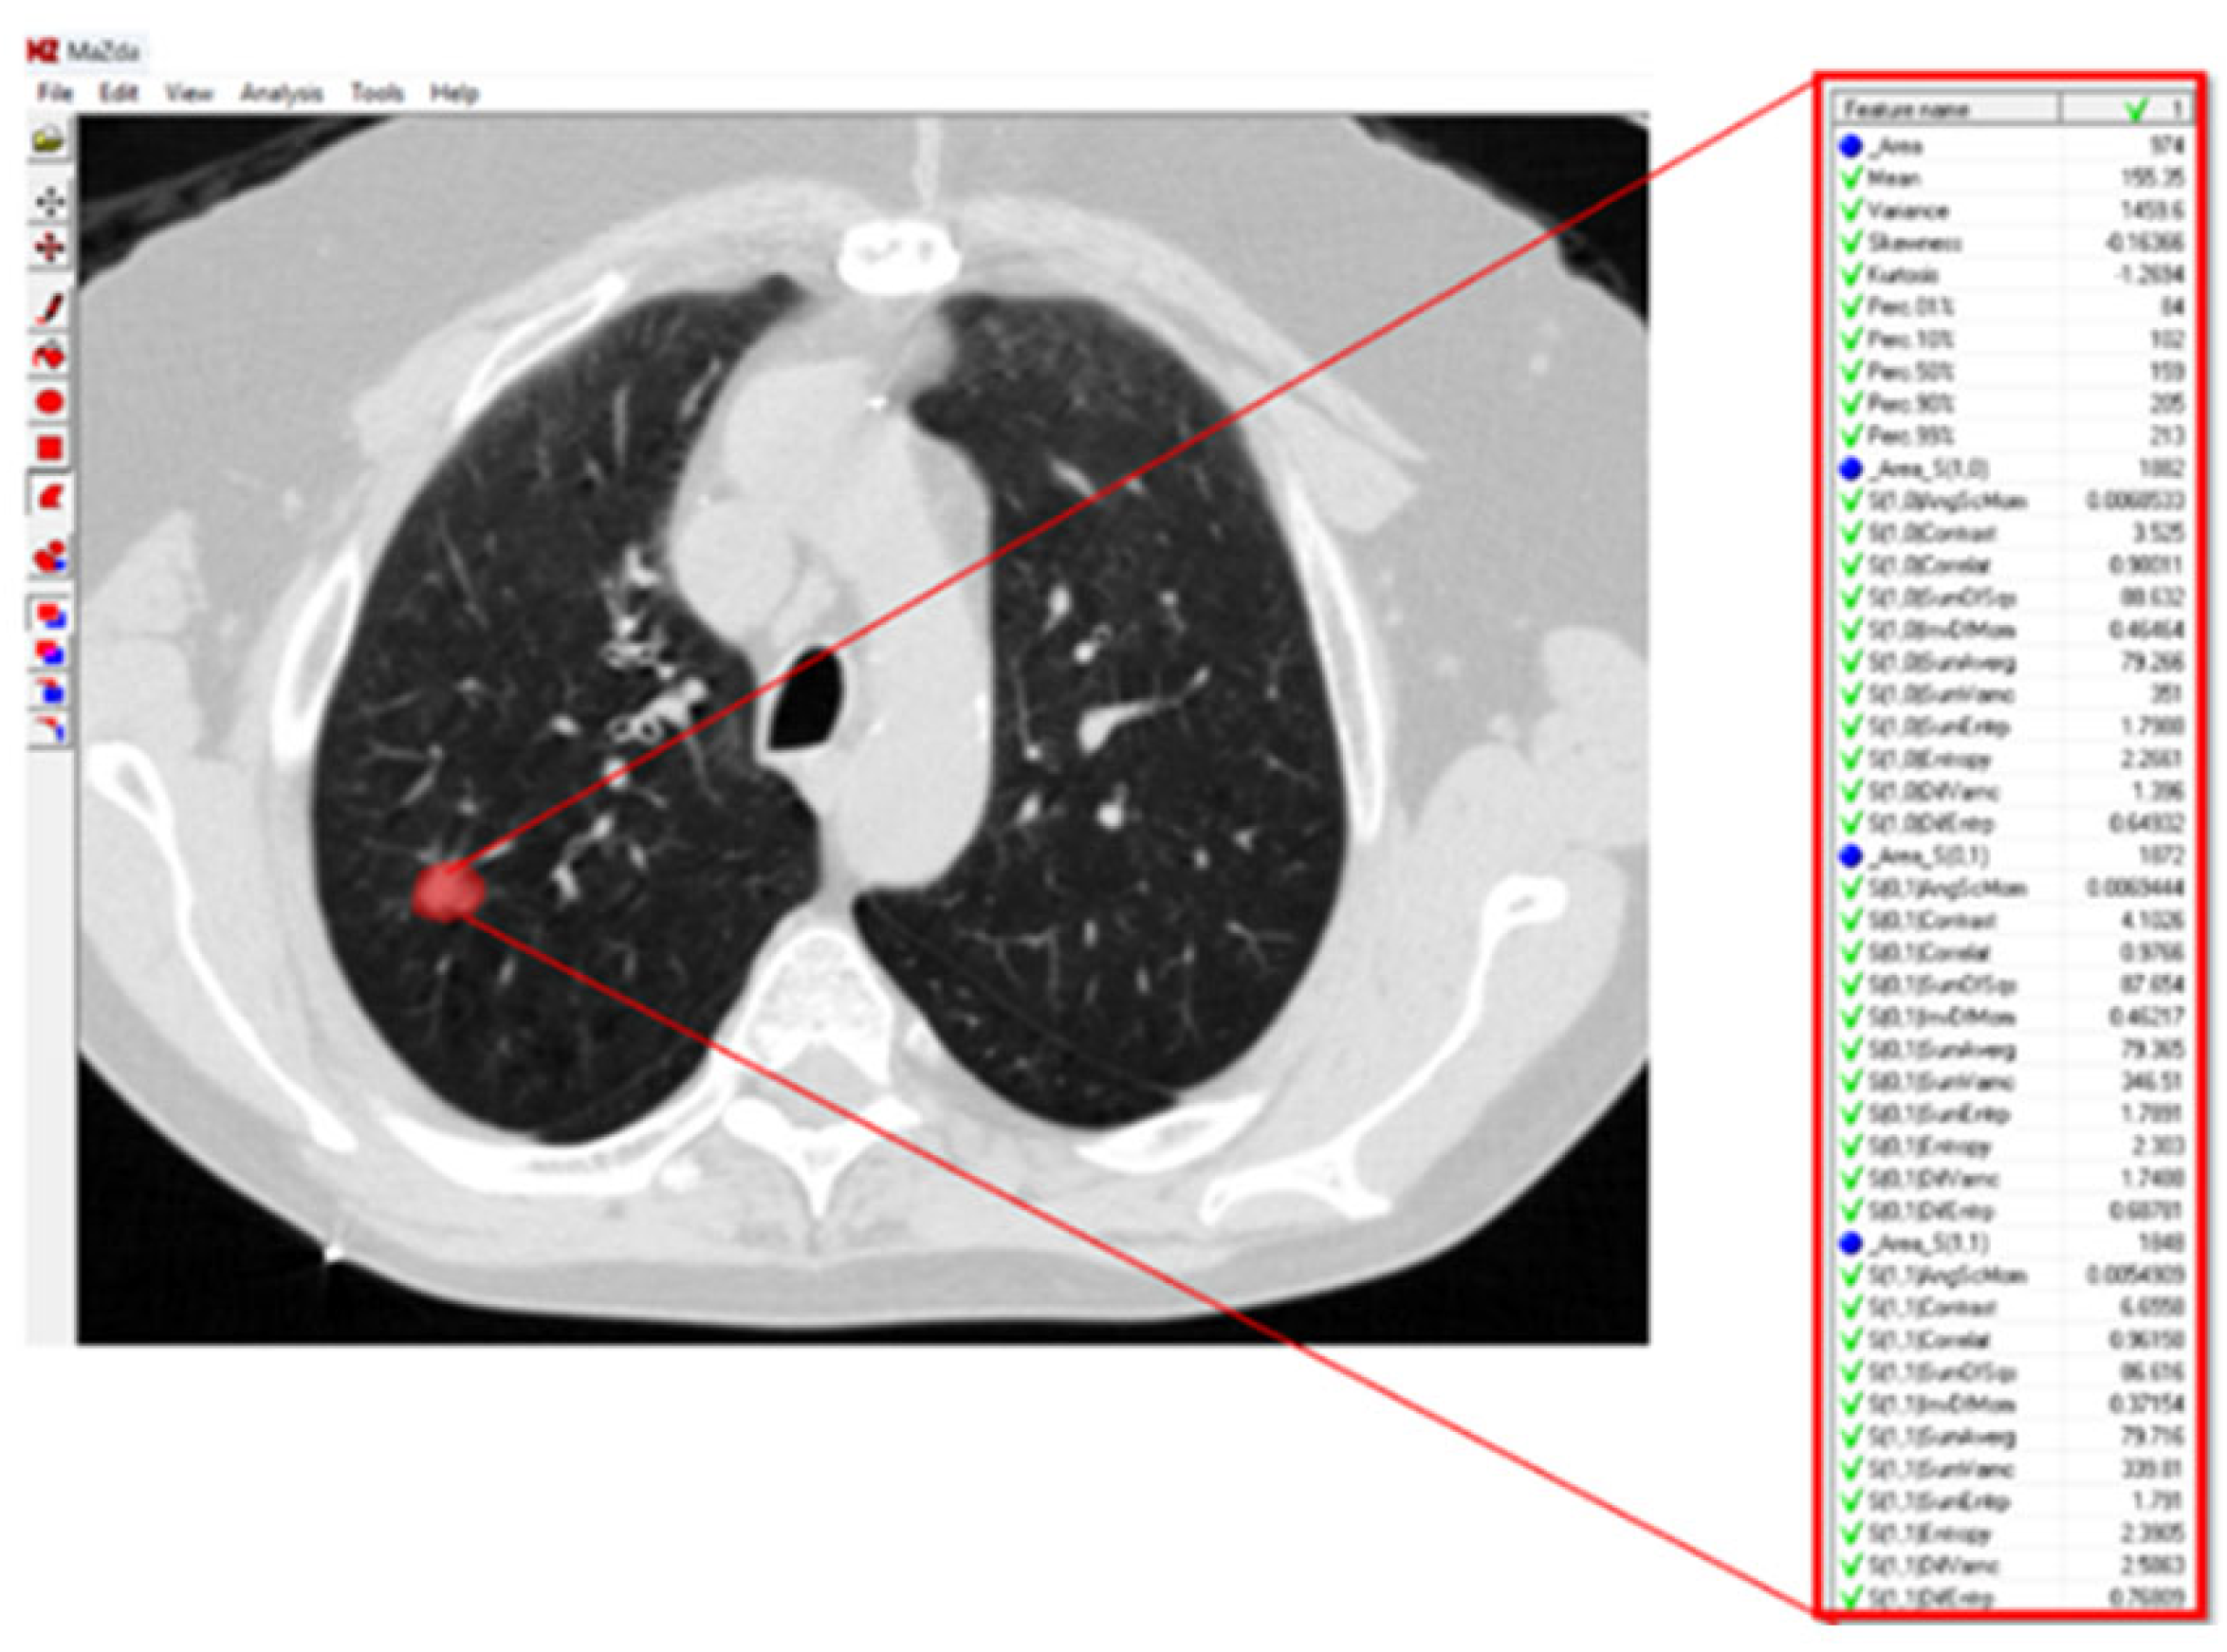

For texture analysis, a digital technology called MaZda (version 4.6) was used [27]. To calculate the texture variables of the GGO lesions in the radiographic image, an annotation of the tumor region was performed. Subsequently, the software calculated the texture variables (Figure 1).

Figure 2. Lung CT scan with GGO texture analysis. About one-third of the variables extracted by the MaZda 4.0 software for the texture analysis of the GGO in this lung CT scan are presented. The red circle denotes the GGO region of interest.

Jcm 14 08082 g002